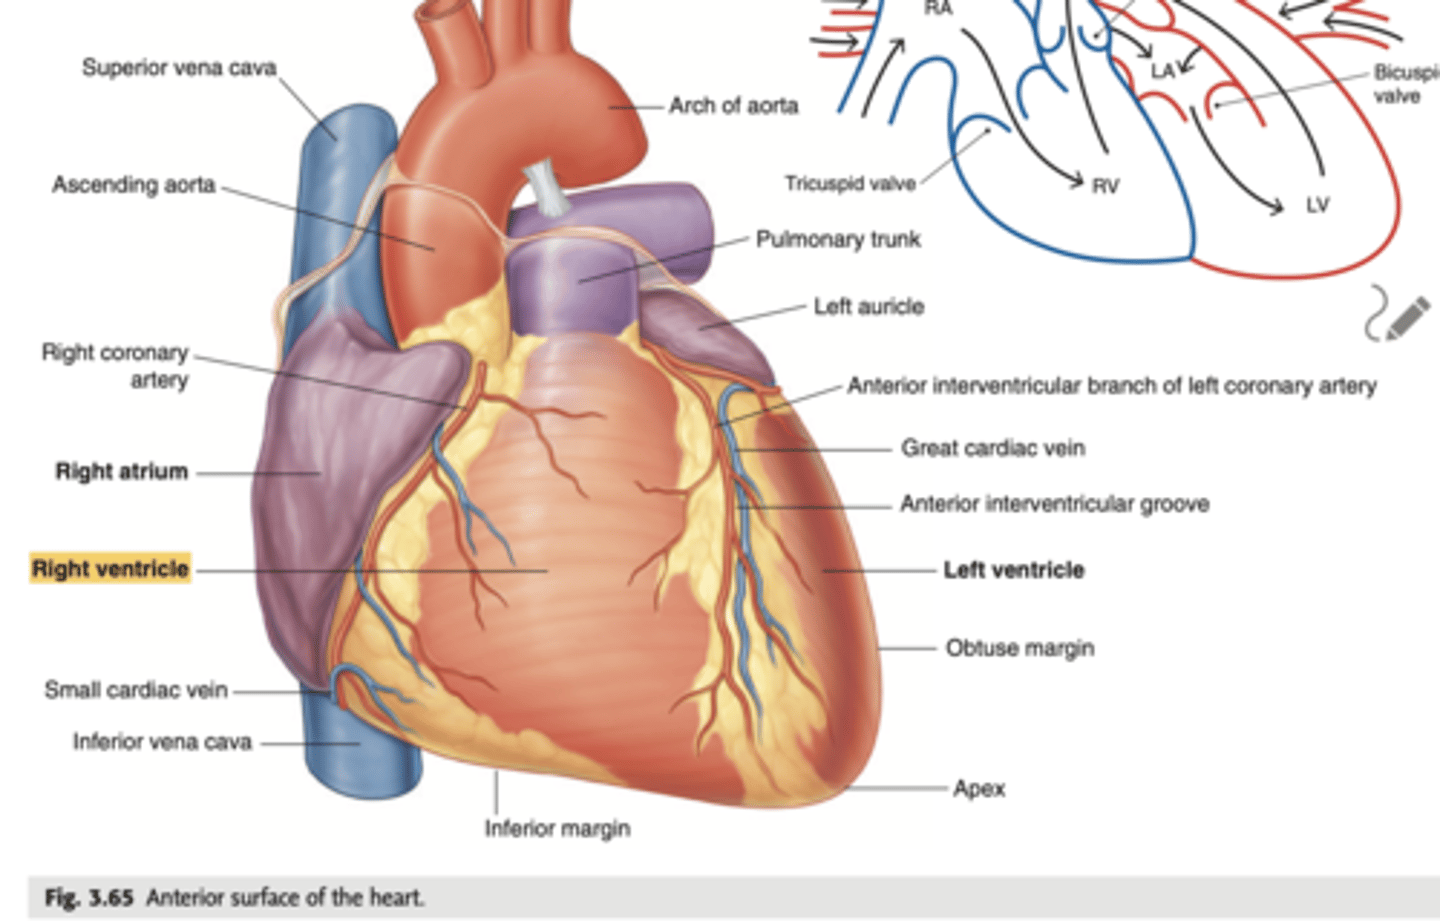

Describe the apex in the heart's anterior view

. Point to left side, downwards.

. At the level of the 5th intercostal space (we will auscultate the apex of the left ventricle)

Describe the Sternocostal Surface

Most of the anterior surface of the heart corresponds to the right ventricle.

What are the atrial appendages?

Rough trabeculated region of the atria (Extensions of the atria)

External portions of the atria, (Real cavities of the right and left atrium being posterior to these auricles)

ALSO CALLED AURICLES

Describe the location of the main arteries in the anterior view of the heart

The pulmonary trunk exits the right ventricle

. aorta exits the left ventricle.

During early heart development, the pulmonary artery is on the left and the aorta on the right because they develop from a common tube (truncus arteriosus).

What is the pulmonary trunk?

. major blood vessel that plays a crucial role in the circulatory system by carrying deoxygenated blood from the heart to the lungs.

. Divides into left and right pulmonary arteries